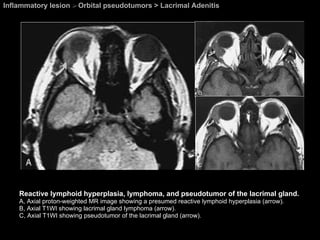

Inflammatory lesion  >  Orbital pseudotumors > Lacrimal Adenitis Reactive lymphoid hyperplasia, lymphoma, and pseudotumor of the lacrimal gland.  A, Axial proton-weighted MR image showing a presumed reactive lymphoid hyperplasia (arrow).  B, Axial T1WI showing lacrimal gland lymphoma (arrow).  C, Axial T1WI showing pseudotumor of the lacrimal gland (arrow).

Lacrimal Adenitis Orbital pseudotumors  Presents with tenderness in the upper outer quadrant of the orbit in the region of the lacrimal gland. Because of the wide variety and incidence of pathology that can involve the lacrimal gland,  biopsy of this accessible site is necessary to obtain a definitive diagnosis.